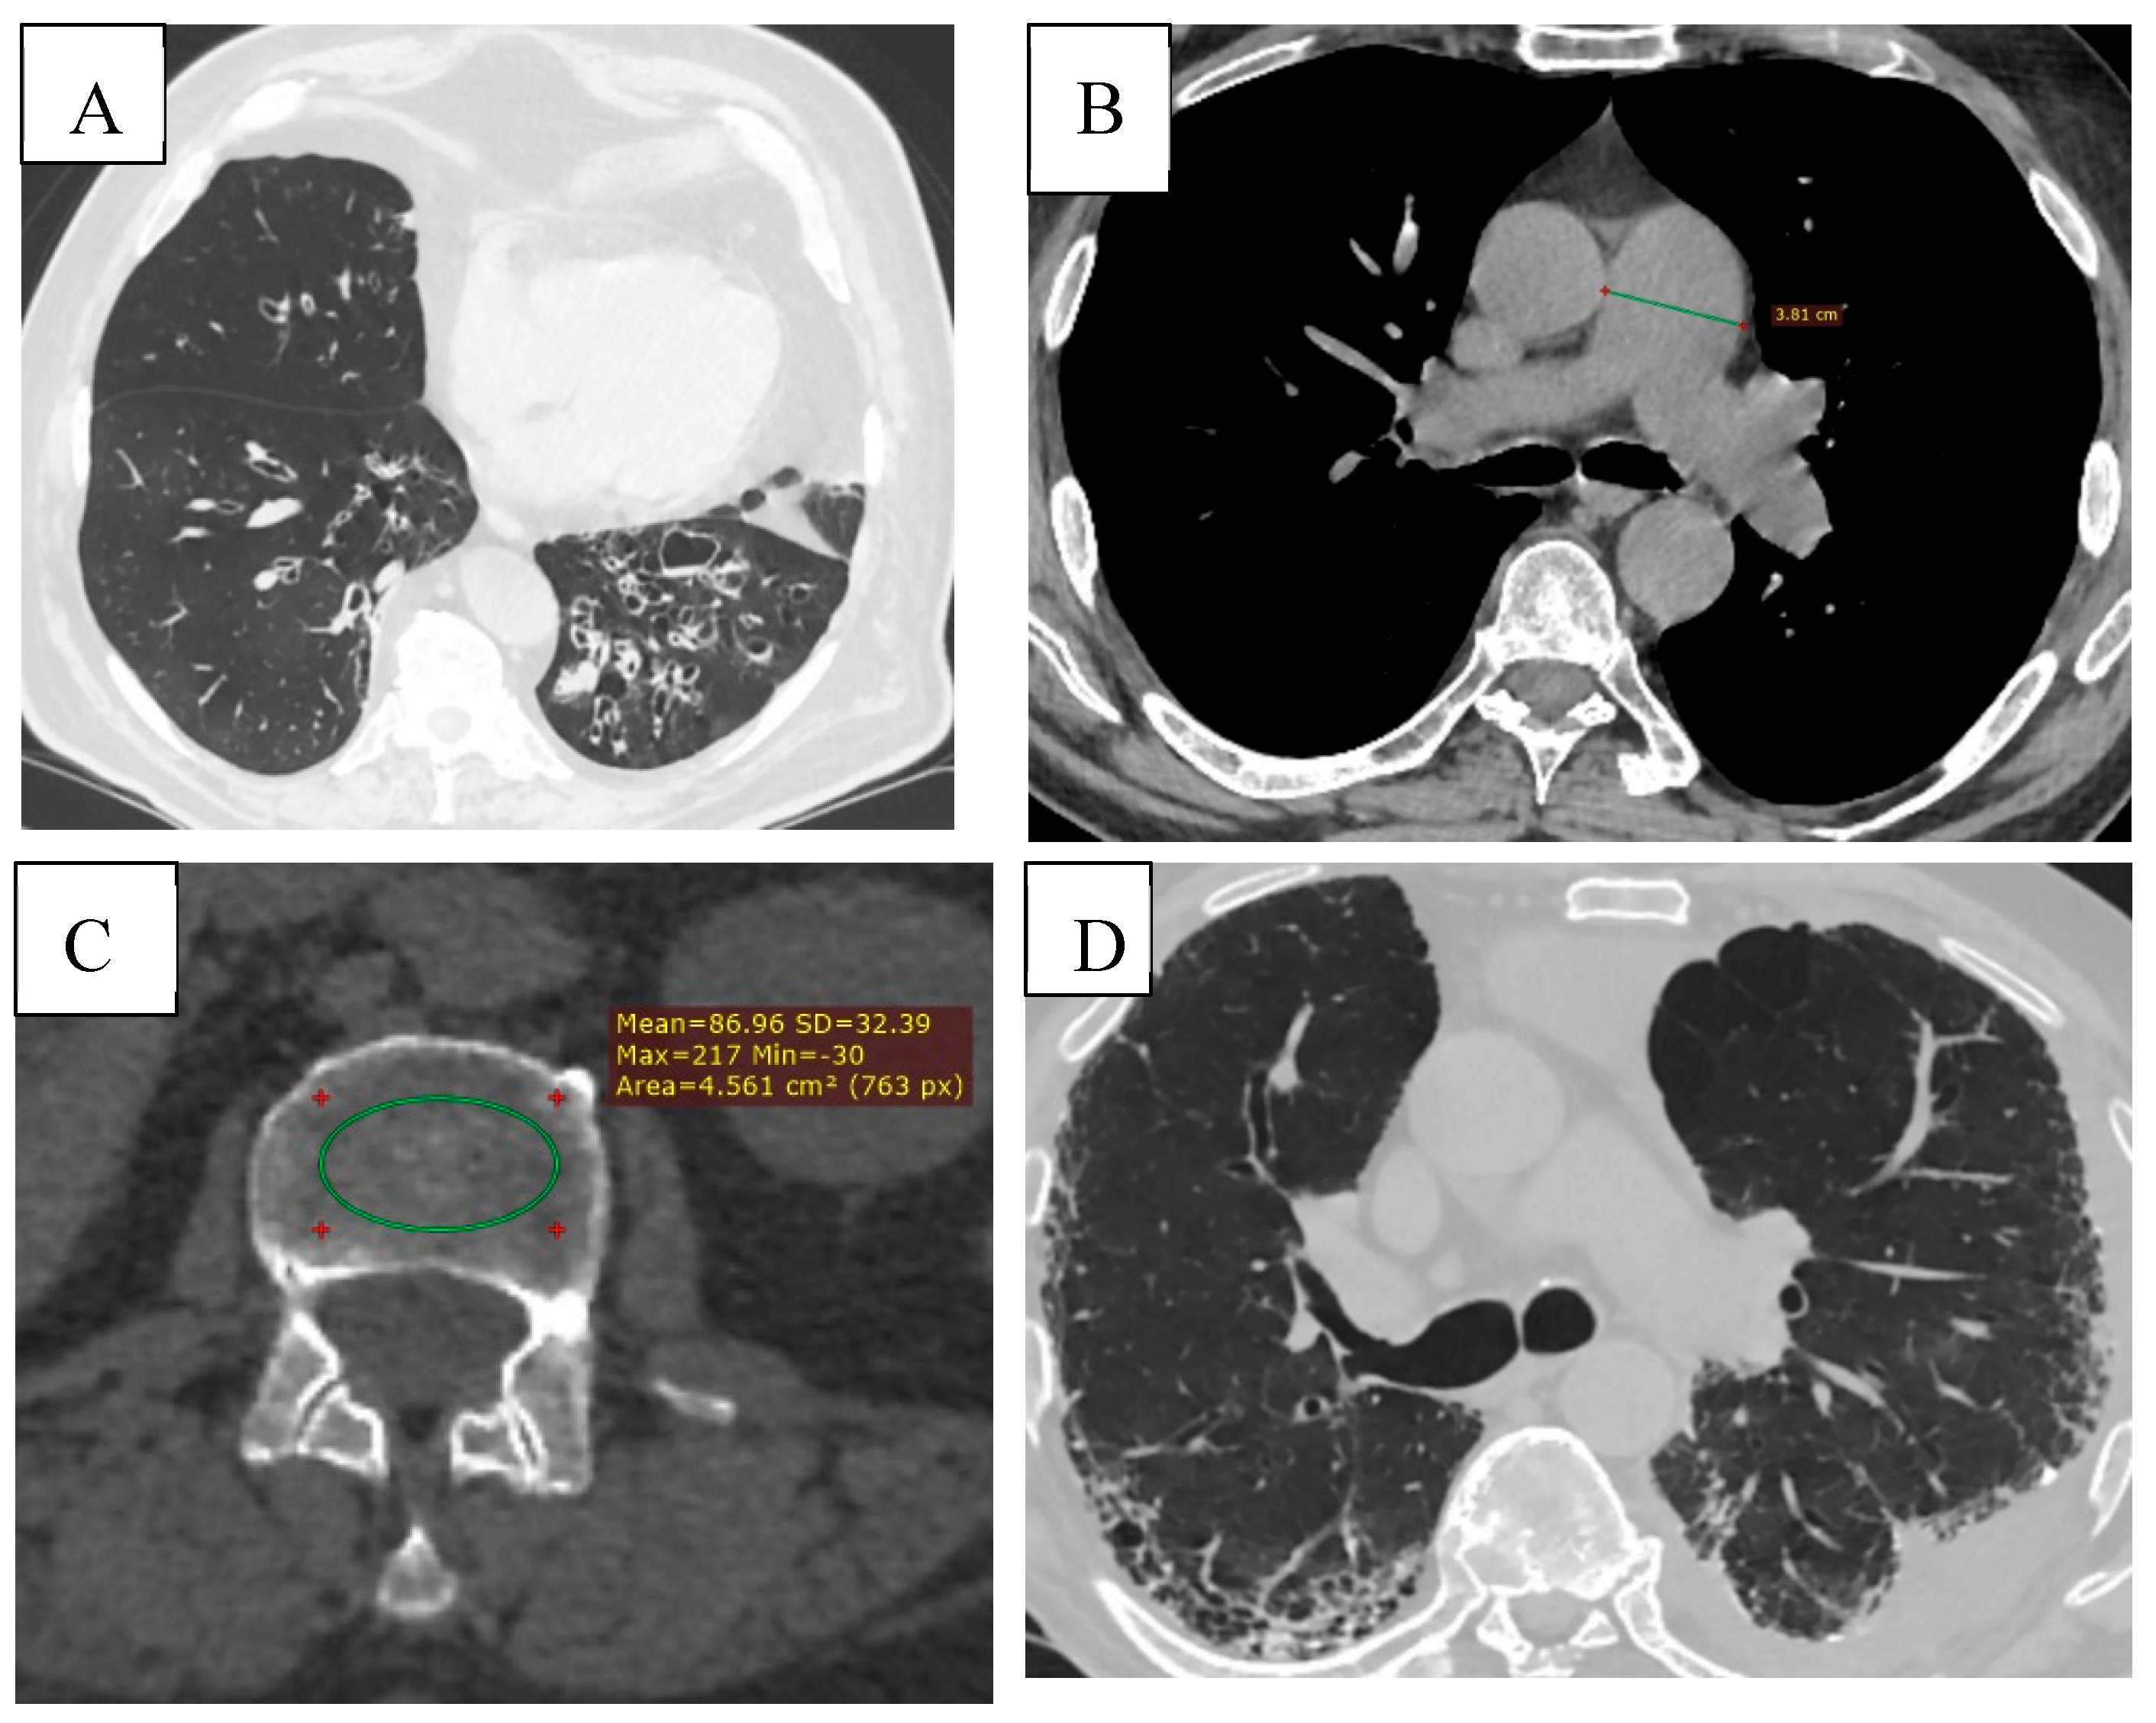

As depicted in Figure 6, chest CT further revealed a wide spectrum of comorbidities, including bronchiectasis, pulmonary artery enlargement, osteoporosis, and interstitial lung disease.

Figure 6. (A) Bronchiectasis (multiple types of bronchiectasis in the lower lobe of the right lung, some with mucoid impaction). (B) CT signs of pulmonary hypertension (diameter of the pulmonary trunck 3.8 cm (normal < 2.9cm). (C) Osteoporosis, bone density measurement at the level of L3 (86.96 HU). (D) ILD (Interstitial Lung Disease), subpleural honeycombing formed by clustered cysts stacke together in several layers. Reticular pattern. Left pleural effusion.